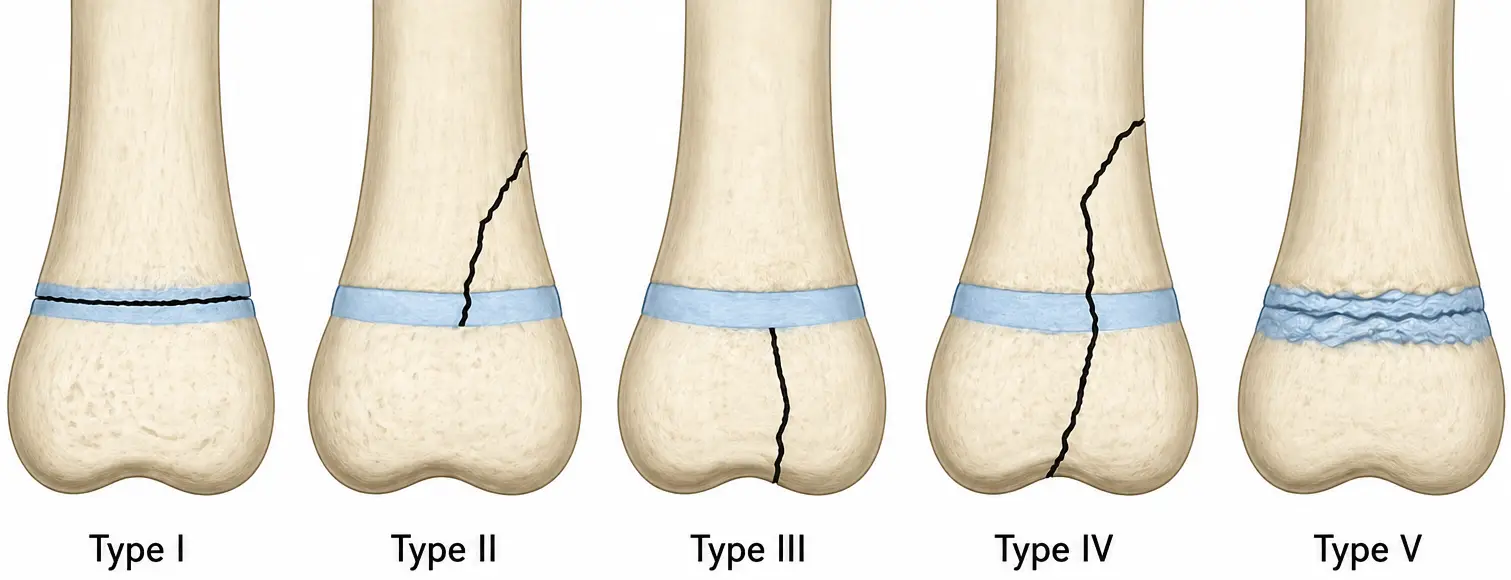

Salter-Harris fracture

Salter-Harris fractures are classified into five types based on the location and extent of the fracture:

- Type I: Separation of the epiphysis from the metaphysis through the growth plate

- Type II: Fracture extends from the growth plate into the metaphysis

- Type III: Fracture extends from the growth plate into the epiphysis

- Type IV: Fracture extends from the growth plate through both the epiphysis and metaphysis

- Type V: Crush injury of the growth plate